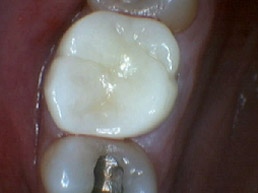

Bruxir Crowns